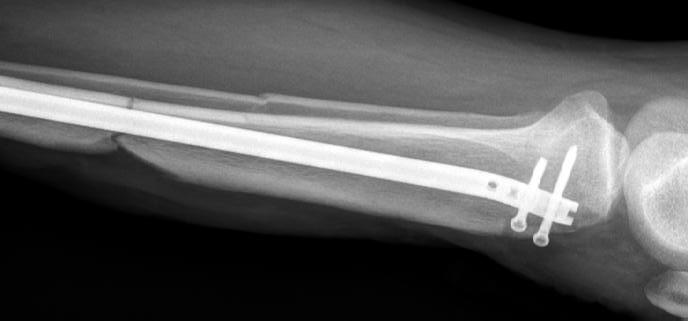

Osteosinteza preventive (Figura 1) reprezintă o opțiune importantă în cazul leziunilor metastatice osteolitice extinse, care amenință integritatea osului și care prezintă un risc ridicat de fractură. Procedurile de osteosinteză, cum ar fi utilizarea tijei centromedulare sau plăcilor de fixare, sunt eficiente pentru stabilizarea oaselor lungi, precum femurul sau humerusul, unde metastazele osoase sunt frecvent localizate. În plus, în zonele cu distrucție osoasă semnificativă, cimentul acrilic (PMMA) poate fi utilizat pentru a crește rezistența biomecanică a osteosintezei și pentru a preveni instabilitatea post-operatorie (9,13) .

Figura 1: Cazul unei femei de 66 de ani, cu probleme de sănătate complexe, care a suferit o fractură patologică la nivelul humerusului din cauza unei metastaze. (A) Evidențiază metastaza osteolitică din humerus. (B) Imagine scintigrafică ce arată răspândirea sistemică. (C) Imagine postoperatorie care prezintă o tijă centromedulară utilizată pentru osteosinteză, permițând mișcarea imediată a brațului.